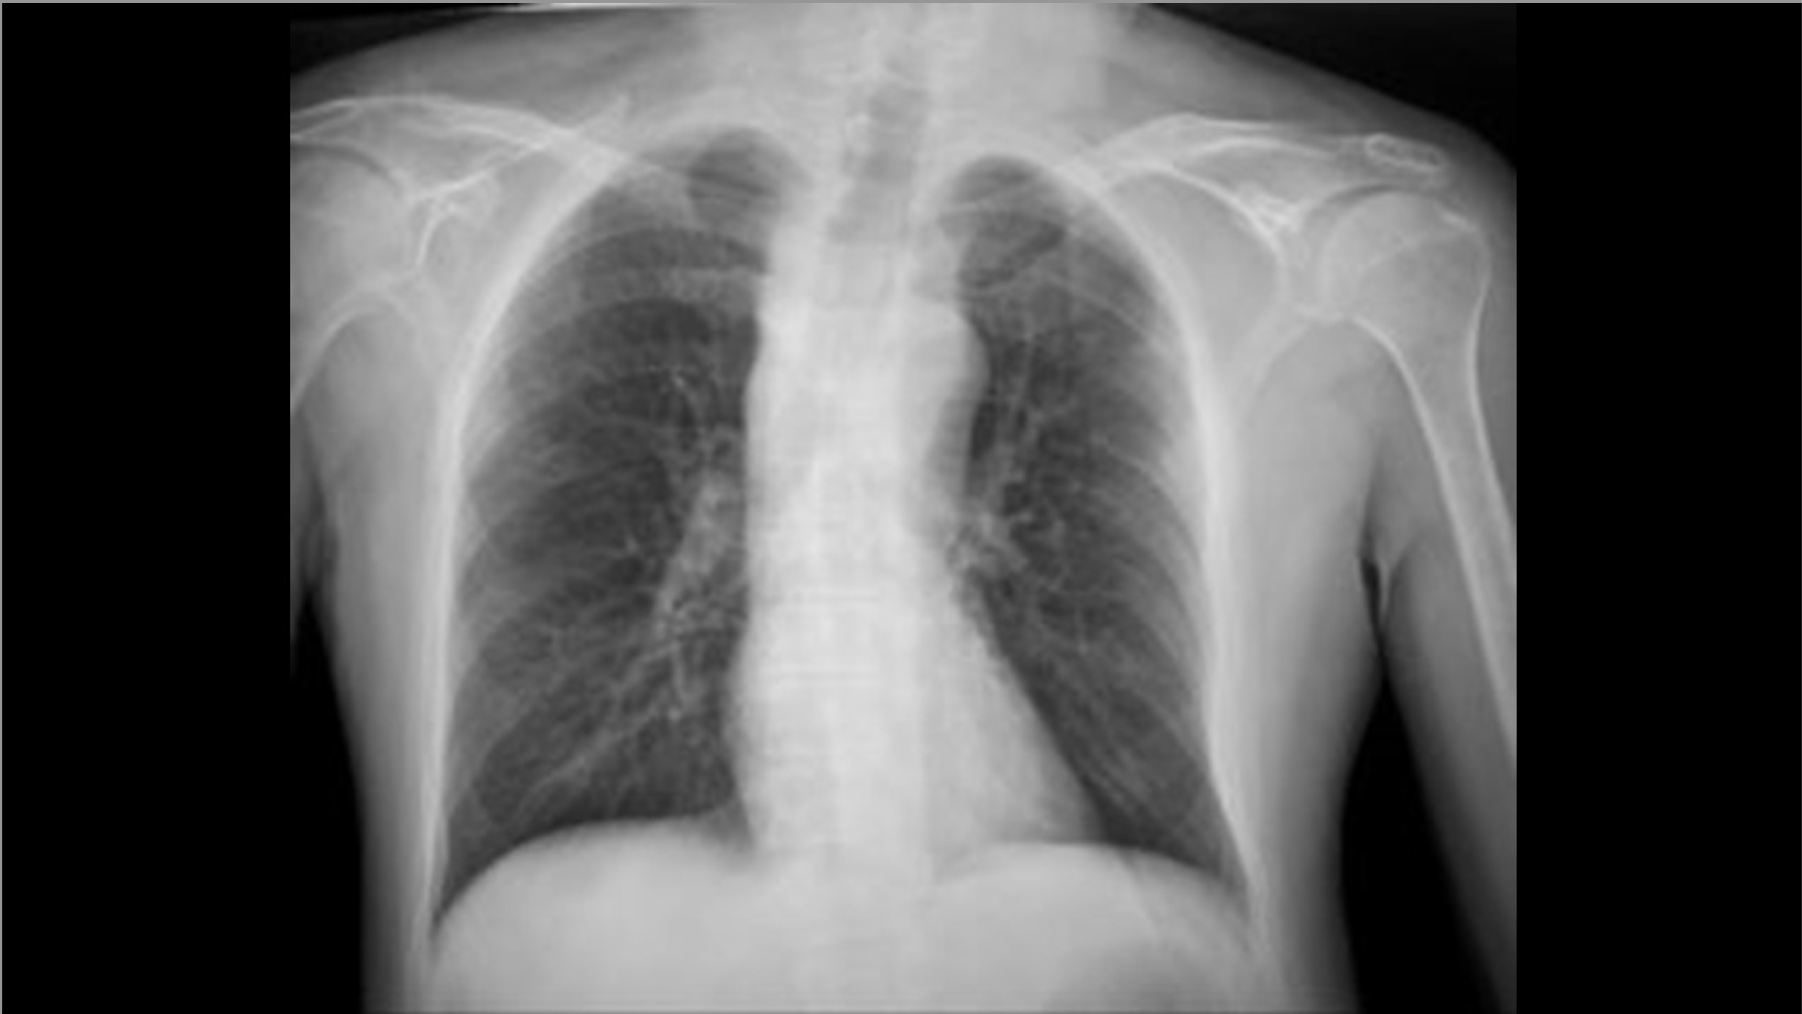

Caso 02